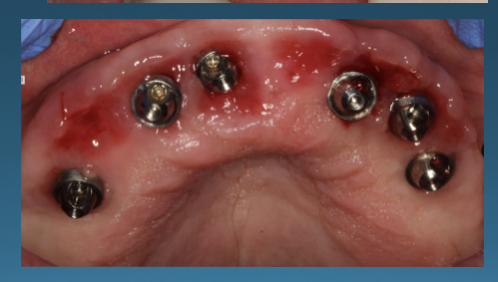

(42.) Fixed-removable prosthesis.

Figure 42

(43.) Fixed-removable prosthesis.

Figure 43

(44.) Fixed-removable prosthesis.

Figure 44

(45.) Fixed-removable prosthesis.

Figure 45

At the initial patient examination, several factors in addition to restoration shape should be considered when planning implant-supported restorations. History of periodontal disease, irregular maintenance visits, clinical appearance of the remaining teeth and soft tissue conditions may indicate increased risk of peri-implantitis. Patient dexterity, adaptability, willingness, and capability to carry out intended home care should be considered. Patient's mental conditions including dementia may influence the design of this as well as unrealistic patient expectations. A "High water original Branemark design" or no treatment may be indicated. Especially when implant location makes access, a fixed-removable design may be necessary to reduce risk of peri-implantitis may be indicated (Figures 42 through Figure 45). Considering that oral biofilm accumulation, even at two weeks post prosthetic insertion is documented, periodic removal of screw retained restorations is less effective than daily access to disrupt bacterial plaque accumulation.